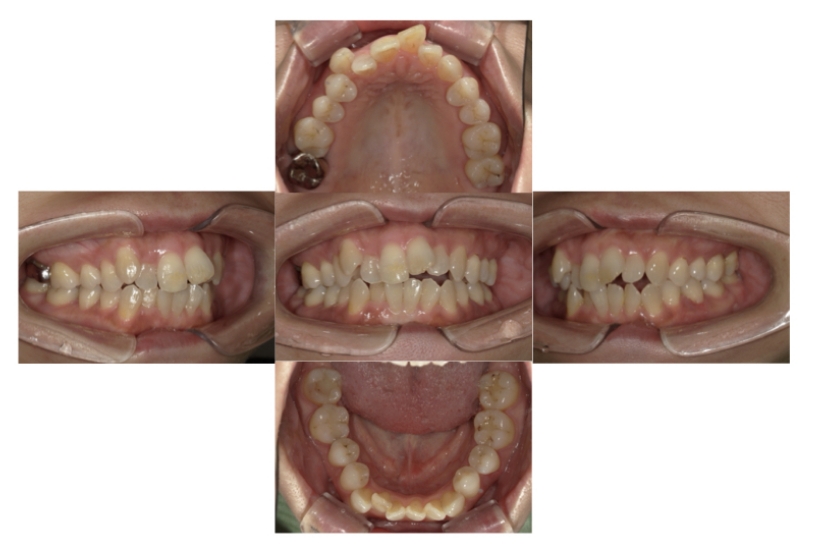

症例3

叢生

抜歯

ブラケット矯正

上下顎叢生(上下の前歯のガタガタ)のケースです。

装置はラビアル(上下表側)で、上下顎の小臼歯を4本抜歯を行っています。抜歯したスペースを使って、上下の前歯の後方移動と叢生(ガタガタ)の改善を行っています。

主訴 八重歯を治したい。

年齢・性別 25歳 女性

お住まいの地域 神奈川県川崎市

治療方針 抜歯スペースを利用して上前歯の叢生(ガタガタ)の改善

抜歯部位 上下顎左右第一小臼歯

使用装置 ラビアル(上下表側)、顎間ゴム

治療期間 1年11か月

治療回数 16回

リテーナー クリアリテーナー

BEFORE

AFTER